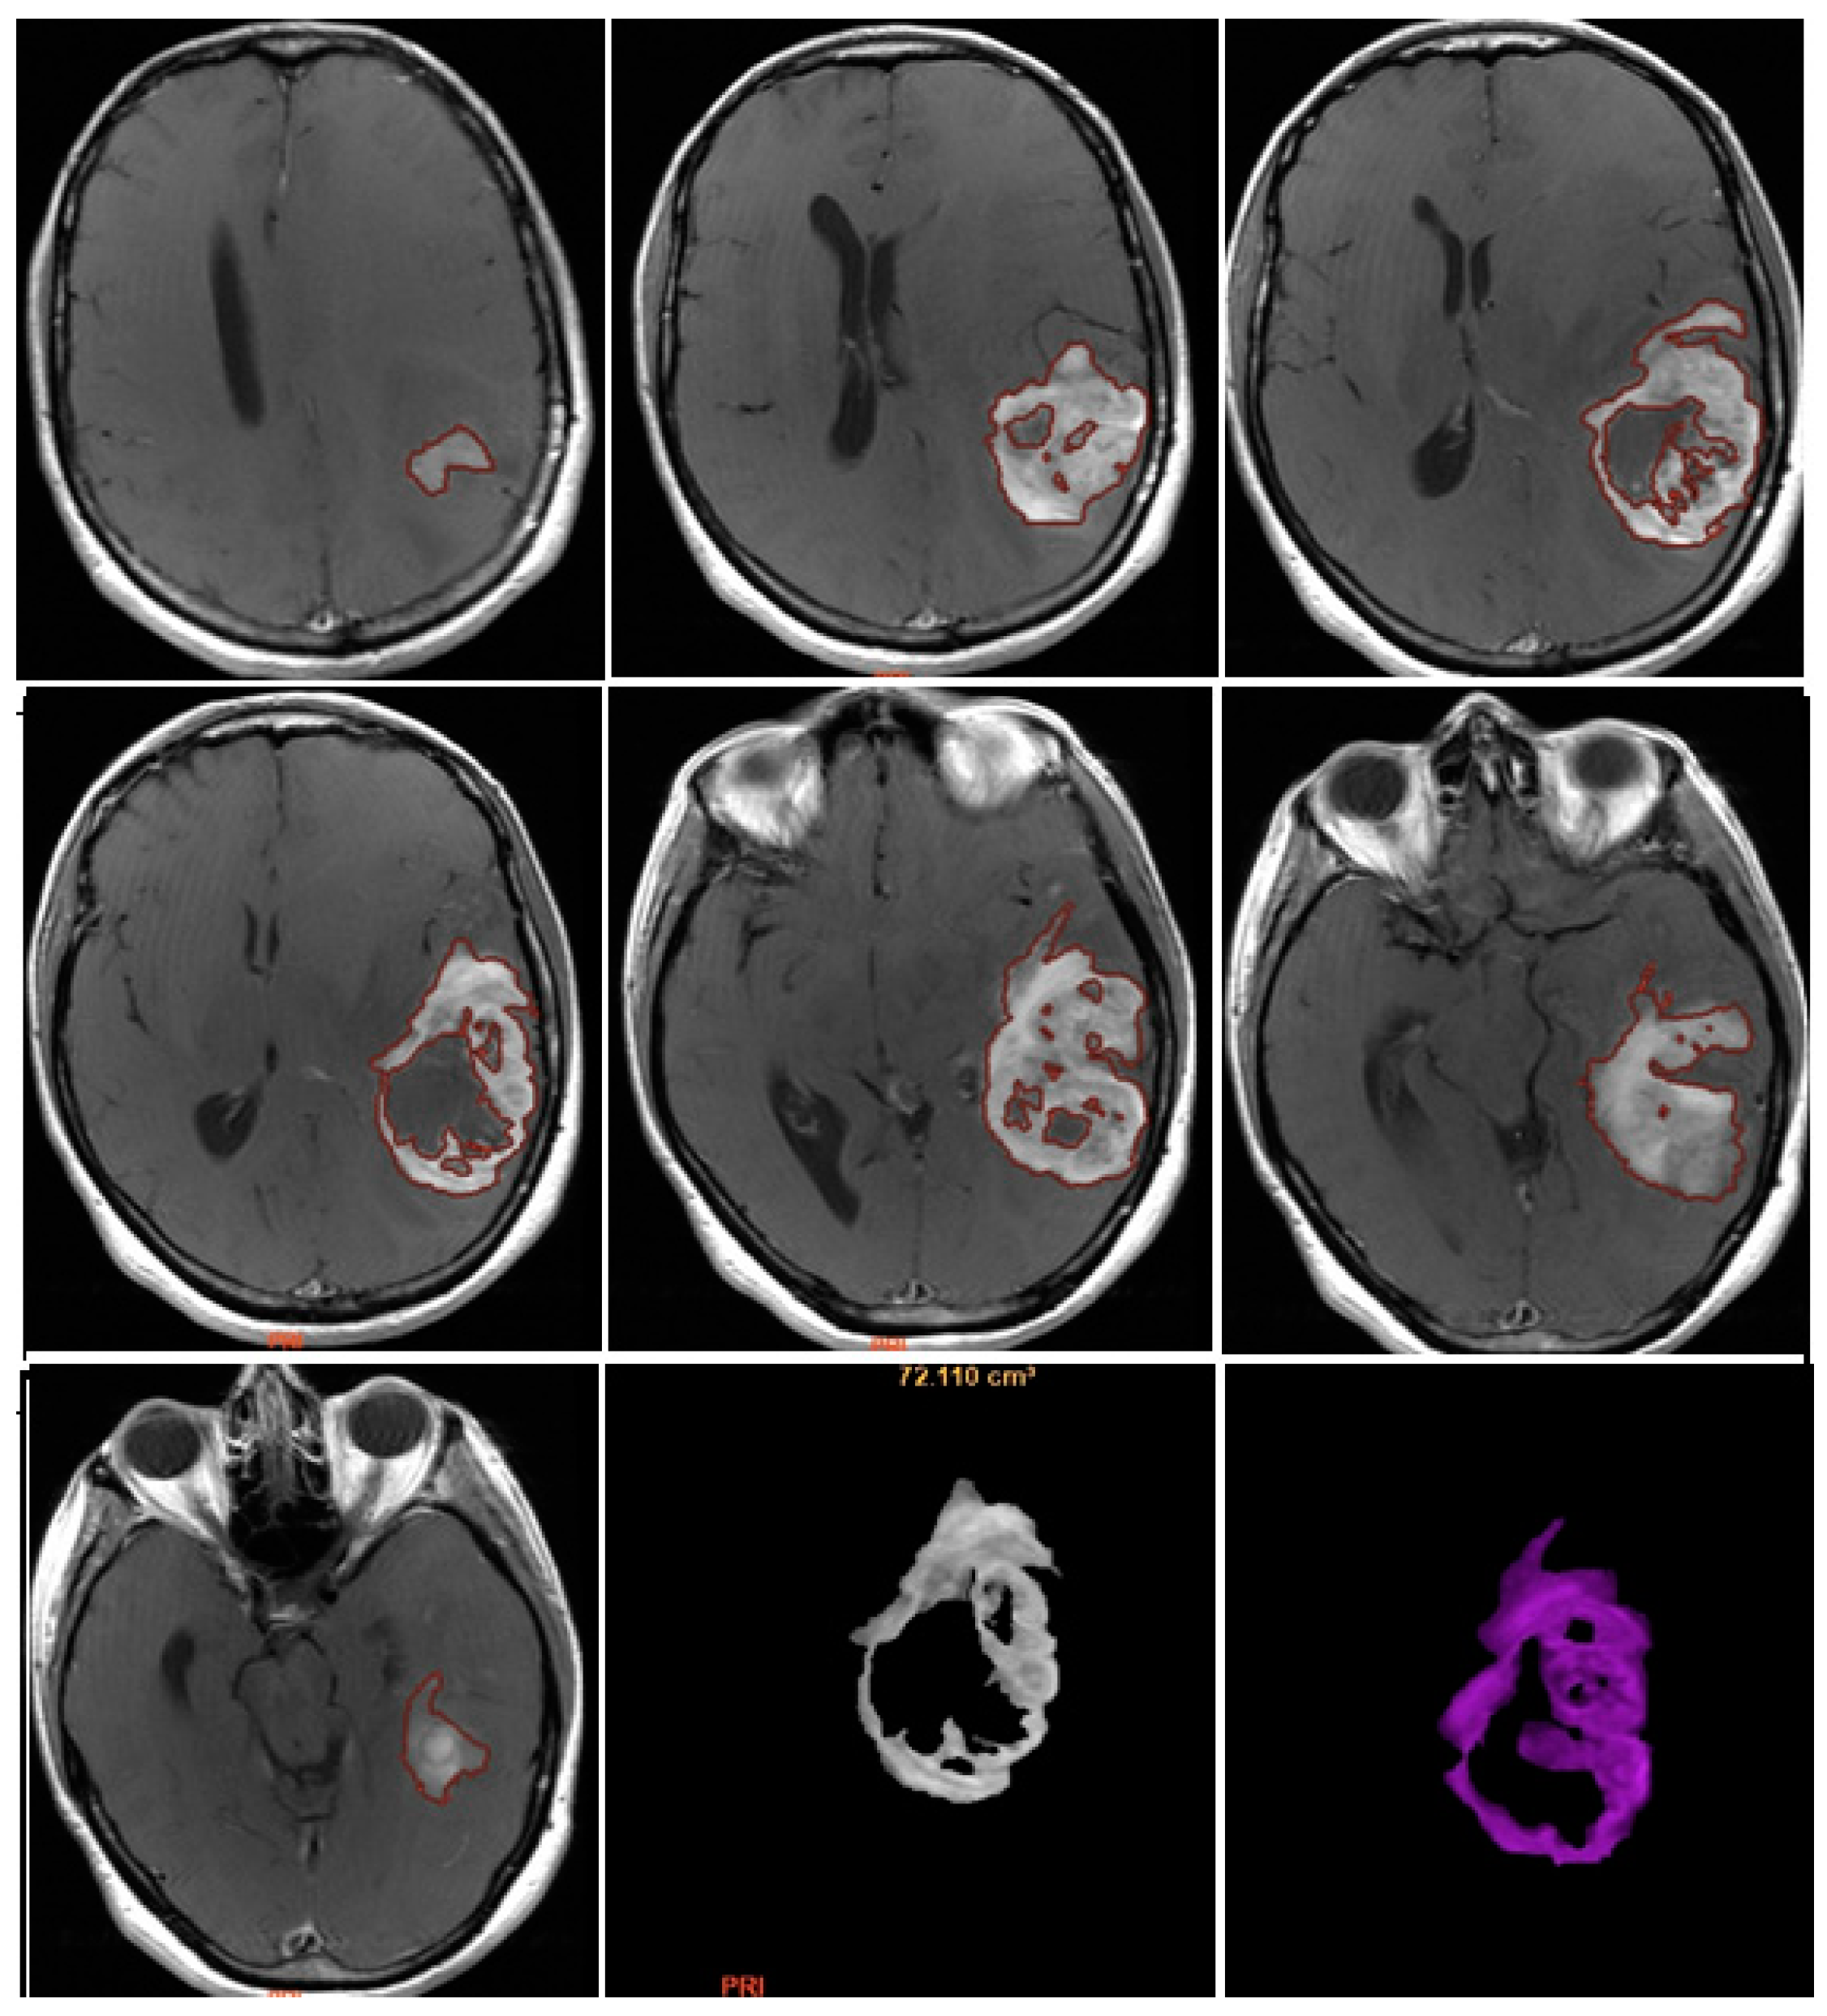

T2/FLAIR-PV and T2/FLAIR-RV were both evaluated manually on axial hybrid sequences resulting from FLAIR (slice thickness: 5 mm.; slice spacing: 5,5 mm.) and CE-T1w (slice thickness: 5 mm.; slice spacing: 5,5-6 mm.) fusion, in order to measure exclusively the edema/infiltration component, excluding the tumor enhancing mass previously assessed with CE-PTV and CE-RTV measurements [Figure 5 and Figure 6].

NV was evaluated manually on preoperative 2D axial CE-T1w images, including only the necrotic area inside the tumor [Figure 7].

TV was calculated as the sum of NV and CE-PTV, both assessed on 2D axial CE-T1w images (slice thickness: 5 mm.; slice spacing: 5,5-6 mm.).

Figure 5. Edema/Infiltration Preoperative Volume (T2/FLAIR-PV).

Preprints 86216 g005

Figure 6. Edema/Infiltration Postoperative Volume (T2/FLAIR-RV).

Preprints 86216 g006

Figure 7. Necrosis volume inside the tumor.

Preprints 86216 g007